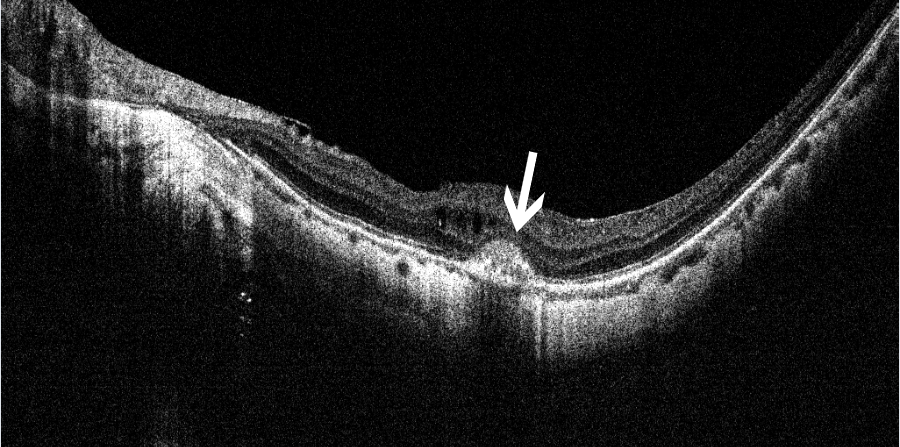

黄斑裂孔(全层)

眼科ab超检查单怎么看常见眼底疾病检查结果的秒懂解读_https://www.jmylbn.com_新闻资讯_第7张这个病就是老百姓说的“眼底有个眼儿”或“视网膜膜裂了”,其实就是指黄斑部视网膜的前9层发生的组织缺损,形成个小孔。

OCT:裂孔处无组织无光反射,呈黑色

图片来源:天津市眼科医院